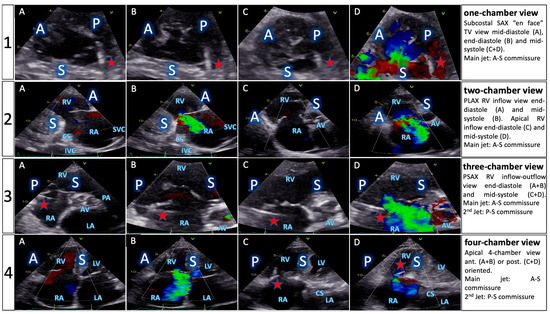

| TTE View | Focus | ||

|---|---|---|---|

| Functional Parameters | Right Heart Morphology | TV Anatomy | |

| PLA standard | LVOT diameter (Qs/CO calculation) | RV function and size (eyeballing) | -- |

| PLA RV inflow RH two-chamber view | TR severity (eyeballing) TR Jet VC and PISA (optional) | RV function and size (eyeballing) | AL visualization SL vs. PL distinction |

| PSA standard RH three-chamber view | TR severity (eyeballing) RVOT VTI RVOT diameter | RV size PA size | Leaflet distinction, if possible |

| PSA-modified alternative RH one-chamber view | TR severity (eyeballing) | TV annulus size Coaptation gap | Simultaneous visualization of all leaflets |

| A4C RH four-chamber view | TR Jet area, VC and PISA TR VTI, RVSP TAPSE RV free wall TDI RV FAC RA volume RV diameters LVOT VTI (A5C/A3C) | RV function and size RA size TV annulus size Tenting height | SL visualization AL vs. PL distinction |

| A2C right alternative RH two-chamber view | TR Jet area, VC and PISA | RA size TV annulus size | AL visualization |

| Subcostal long axis | Hepatic systolic vein flow reversal Inferior vena cava size | RV function and size (eyeballing) | PL visualization AL vs. SL distinction |

| Subcostal short axis RH one-chamber view | TR severity (eyeballing) | Coaptation gap | Simultaneous visualization of all leaflets |